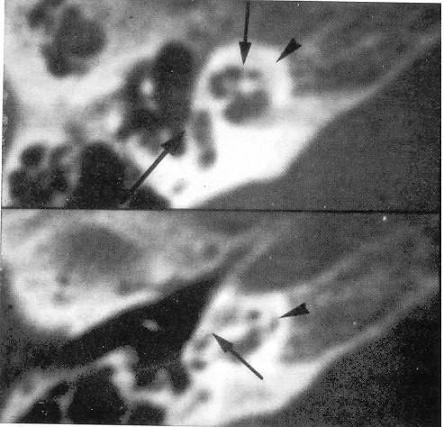

Estudiamos 6 pacientes con fracturas laberínticas y cofosis. En 4 pacientes encontramos neumolaberintos, hallazgo que confirma fractura del oído interno (fig.2) (fig.3).

Figura 2. Fracturas Laberínticas

Figura 3. Fractura que afecta el vestíbulo coclear